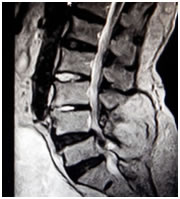

On lumbar MRI, overall prevalence of lumbar degenerative findings was disc bulge (figure 2) 125 (75.75%), nerve root compression 66 (40%), and central canal stenosis 44 (26.66%). The least common finding was disc herniation (figure 1) which was seen in 31 patients (18.78%) (Fig.1and2). Minority of participants 15 (9.09%) had normal lumbar MRI findings (Fig. 3).

Figure 1: Shows degeneration of intervertebral disc at L4/L5 level with disc herniation and compression of cord